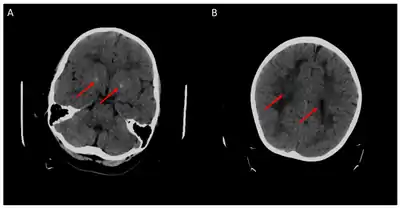

Children with the FOLR1 mutation are born healthy. Symptoms typically appear at about 5 to 24 months of age. The symptoms get worse with time. Without treatment there may be poor muscle tone, trouble with coordination, trouble talking, and seizures.[2][3] In addition, signs of psychomotor retardation, sleep disturbances, cerebellar ataxia, and delayed development of head growth can occur. At around age three, visual disturbances can develop, and sensorineural hearing loss can occur at around age six.[11] In children with cerebral folate deficiency, the cerebrospinal fluid shows low levels of 5MTHF, and a loss of white matter in the brain (leukodystrophy) may occur. As a result of the decreased levels of 5MTHF, the child experiences low levels of Vitamin B folate.[12] There is inability for the 5MTHF to be transported across the blood-brain barrier, resulting in symptoms of seizures, delayed cognitive and motor processing, and autistic features. [13]